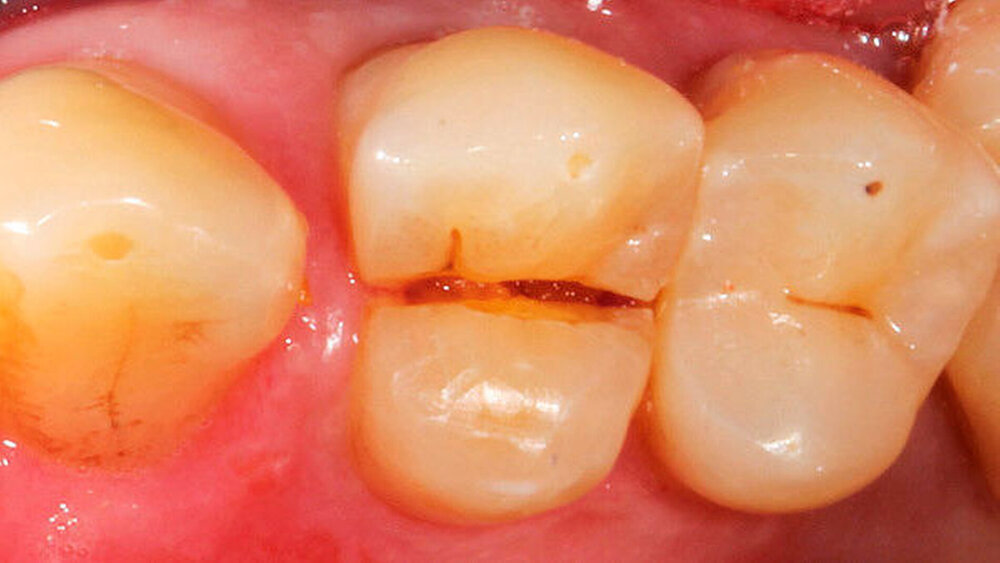

0 | Diagnosestellung (Abb. 1) |

1 | Falls die Diagnose zur Extraktion eindeutig erscheint (wie hier bedingt durch die Längsfraktur der Wurzel): Einkürzen des Zahnes |

2 | Präparation einer Rille in bukkooraler Richtung zur Positionierung der Extrusionshantel (Fa. Komet) (Abb. 2) |